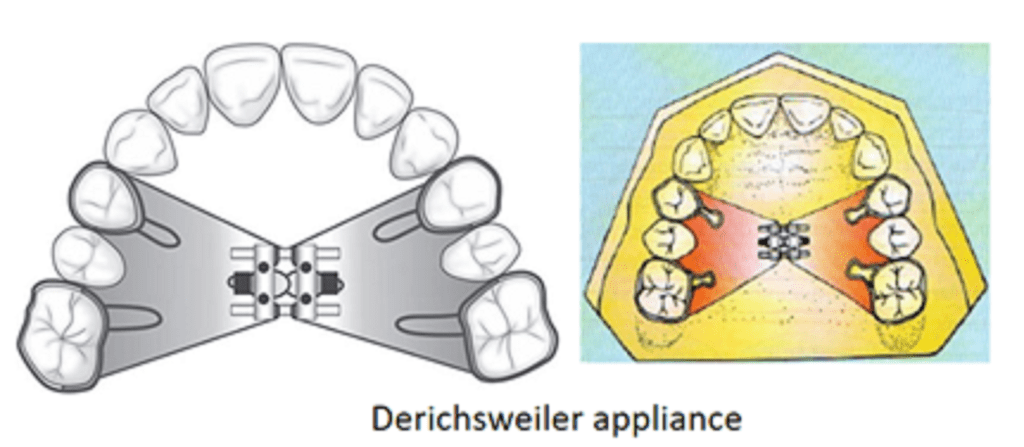

Tooth and tissue-borne appliances: Derichsweiler or the Hass type of appliances

Derichsweiler type: This expansion appliance consists of molar bands on right and left permanent first molars and first premolars with wire tags soldered into the palatal surface. The jack expansion screw is connected to the bands by means of tags that are welded and soldered to the palatal aspect of the band on one side and embedded in acrylic on the palatal aspects of all non-banded teeth except the incisors. Acrylic adapts to the palate and is in two halves to permit activation of the screw in the midline.